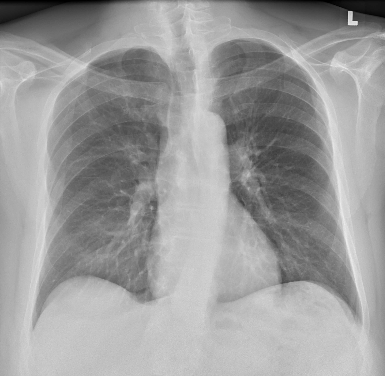

Ik wist al jaren dat mijn houding niet perfect is. Ik loop wat voorovergebogen en mijn postuur is niet bepaald recht als een liniaal. Maar nu heb ik eindelijk fysiek bewijs in handen: een röntgenfoto die onomstotelijk aantoont wat er aan de hand is.

Iedere paar jaar moet ik mijn verblijfsvergunning verlengen. Daar hoort standaard een medische keuring bij, inclusief een bloedtest (om te laten zien dat ik geen HIV heb) en een longfoto om tuberculose uit te sluiten. Meestal krijg ik dan een keurige brief van de dokter waarin staat dat alles in orde is. Maar dit keer ging het anders: ik kreeg een sms met een link naar een app waarin ik zelf de uitslag kon inzien. En daar stond het: mijn longen zijn schoon, mijn ribben heel… maar ook: “thoracic scoliosis convex to the left.”

Met andere woorden: ik heb een verkromming in mijn bovenrug, naar links. Eindelijk weet ik dus waar de pijn vandaan komt, en dat betekent dat ik nu gericht aan de slag kan – met speciale oefeningen en gerichte therapie – om mijn houding te verbeteren en hopelijk de pijn structureel te verminderen. Gelukkig is de verkromming relatief makkelijk te corrigeren.